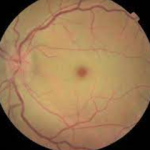

The retina is the nerve layer at the back of your eye that detects incoming light and sends visual signals to your brain.

Retinal diseases such as diabetic retinopathy and age-related macular degeneration (AMD) are among the top leading causes of vision loss and blindness, worldwide.